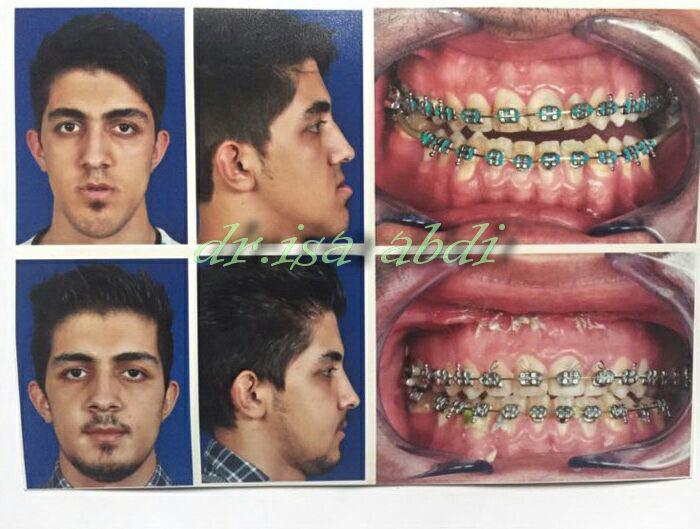

دکتر عیسی عبدی در رشت

– متخصص جراحی فک , پلاستیک صورت و بینی

جراحی فک , پلاستیک , صورت وبینی

چه افرادی نیاز به جراحی فک دارند؟

صورتشان از روبهرو و پهلو تقارن ندارد.

در جویدن و گاز زدن مشکل دارند.